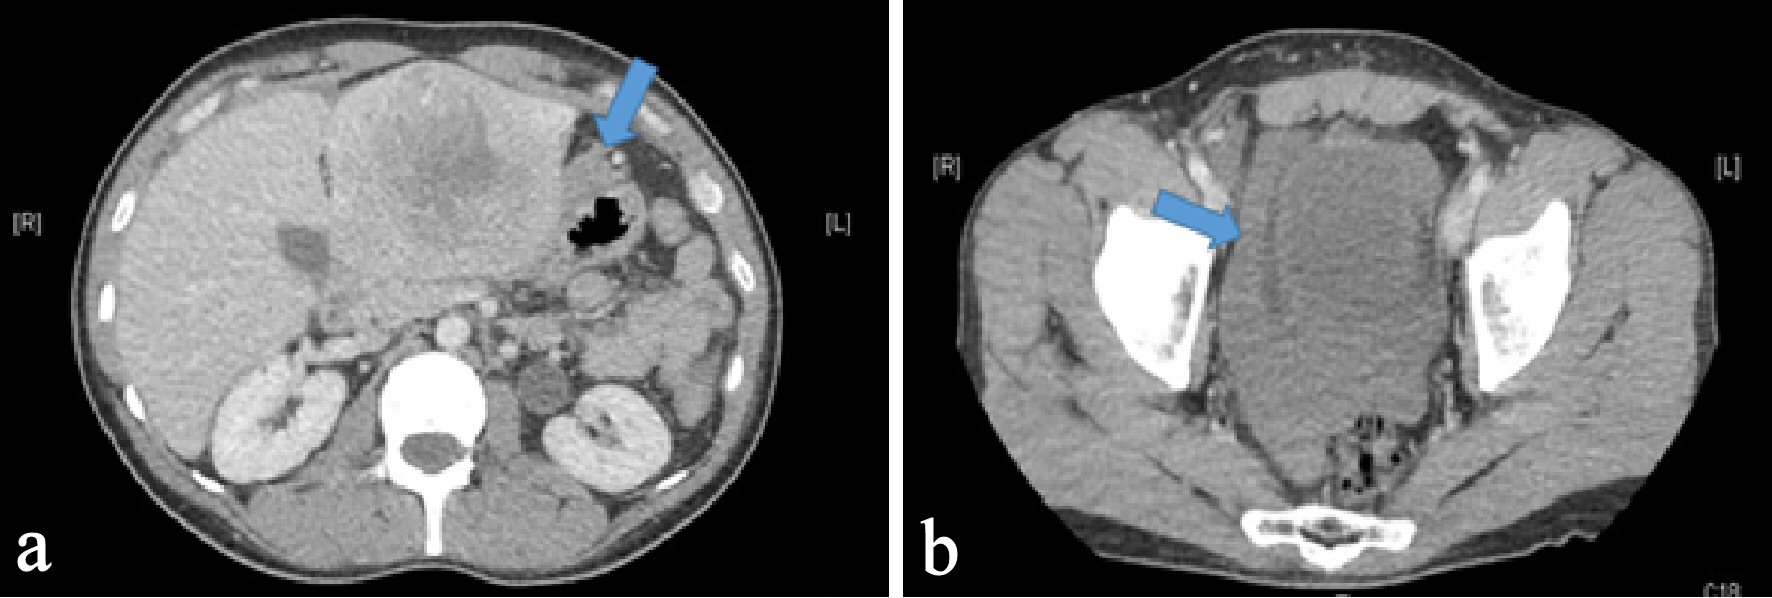

A 37-year-old male with no significant medical, surgical or travel history presented to our emergency room, complaining of severe, sharp epigastric and left upper quadrant pain that started 1 h prior to presentation. He reported no prior trauma, fever, nausea, vomiting, diarrhea or constipation. Physical examination revealed tenderness in the epigastric and left upper quadrants with no palpable masses, guarding or rigidity. His vital signs were stable, with a blood pressure of 159/105 mm Hg and heart rate of 105 beats/min. Laboratory results demonstrated a hemoglobin of 12 g/dL, white blood cell count of 11,000/µL and elevated transaminases (aspartate aminotransferase (AST) of 214 IU/L, and alanine aminotransferase (ALT) of 138 IU/L), alkaline phosphatase (ALP) of 98 IU/L, and total bilirubin of 1.5 mg/dL. Platelets count and coagulation parameters were within normal limits. An abdominal computerized axial tomography (CAT) scan with intravenous contrast revealed an 8 × 7 cm heterogeneous lobulated mass with central hypodensity in the left hepatic lobe with perilesional blood and minimal high-density free pelvic fluid, indicating tumor rupture (Fig. 1). To confirm the diagnosis, the patient underwent computed tomography (CT) angiography, which demonstrated tumor neovascularization from a branch of the left hepatic artery that was successfully embolized using transarterial gelfoam. For further tumor evaluation, magnetic resonance imaging (MRI) of abdomen with liver protocol was performed, revealing a heterogeneously enhancing left hepatic mass (7.7 cm in diameter) with central non-enhancing scar tissue compatible with fibrolamellar variant HCC (Fig. 2). Subsequent biopsy of liver mass confirmed this finding, as malignant hepatocytes filled with ample eosinophilic cytoplasm were observed. These tumor cells are arranged in cords separated by hyaline cartilage, consistent with FLC (Fig. 3). The patient’s hepatitis serology was negative, with normal alpha-fetoprotein level. As the acute symptoms resolved, and the repeat laboratory tests including hemoglobin and liver biochemical tests yielded stable results, he was discharged from the hospital 4 days after admission. Three weeks later, a left hepatectomy was performed uneventfully. Fibrolamellar carcinoma diagnosis was confirmed as well after left hepatectomy. Resected specimen contained a well circumscribed lobulated tumor of 11 × 8 × 7 cm with margins free of tumor. Histopathological diagnosis was also consistent with FHC. Focal hemorrhage and foci of necrosis were present, likely representing prior area of bleeding from tumor rupture.

![]() Click for large image | Figure 1. Axial section of CT abdomen and pelvis with intravenous contrast. (a) An 8 × 7 cm heterogeneous lobulated mass with central hypodensity in the left hepatic lobe with arrow pointing perilesional blood concerning for tumor rupture. (b) An arrow pointing hyperdensity fluid surrounding urinary bladder likely blood from tumor rupture. |